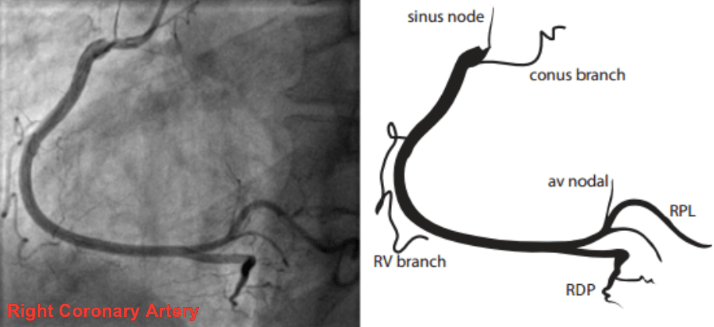

Анатомия коронарных артерий: КТ-изображения